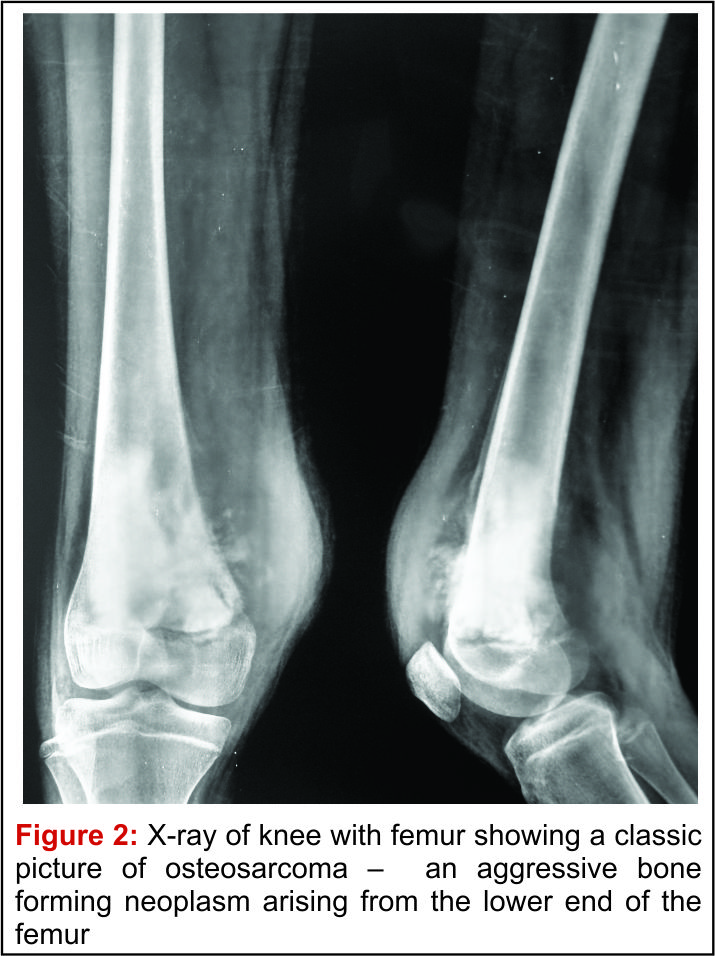

Osteosarcoma Knee - Periosteal Reaction. Imaging characteristics of primary osteosarcoma: Imaging characteristics of primary osteosarcoma: Osteosarcoma is a bone tumor and can occur in any bone, usually in the extremities of long bones near metaphyseal growth plates. Specifically, it is an aggressive malignant neoplasm that arises from primitive transformed cells of mesenchymal origin (and thus a sarcoma). Usually located around the knee in diaphysis or meta/diaphysis and does not occur in hands, feet, spine and flat bones. Children treated with radiation for another cancer also. Osteosarcoma is the most common type of bone cancer, and accounts for about 3% of boys are more likely to have osteosarcoma than girls, and most cases of osteosarcoma involve the knee. Osteosarcoma can cause knee pain or pain and swelling in the affected area. Approximately 800 new cases of. Osteosarcoma is the most common malignant bone tumor.

Approximately 800 new cases of. Osteosarcoma is an aggressive and malignant bone tumor most commonly appearing around the knee and shoulder in adolescents and young adults. Some inherited bone conditions can raise the risk of osteosarcoma. Effects of glucosamine, chondroitin, or placebo in patients with osteoarthritis of hip or knee: Usually located around the knee in diaphysis or meta/diaphysis and does not occur in hands, feet, spine and flat bones. Osteosarcoma is the most common bone cancer in children. Osteosarcoma is the most common type of bone cancer, and accounts for about 3% of boys are more likely to have osteosarcoma than girls, and most cases of osteosarcoma involve the knee. An algorithm recommendation for the management of knee osteoarthritis in europe and internationally. Found as incidental finding or presents with a fracture. Adjuvant multiple drug chemotherapy for osteosarcoma of.

Changes in evidence following systematic cumulative update of research published through january 2009. Approximately 800 new cases of. Results from the cooperative osteosarcoma study group coss of 925 patients. An algorithm recommendation for the management of knee osteoarthritis in europe and internationally. An osteosarcoma (os) or osteogenic sarcoma (ogs) (or simply bone cancer) is a cancerous tumor in a bone. Osteosarcoma is an aggressive and malignant bone tumor most commonly appearing around the knee and shoulder in adolescents and young adults. Osteosarcoma is the most common type of bone cancer, and accounts for about 3% of boys are more likely to have osteosarcoma than girls, and most cases of osteosarcoma involve the knee. Some inherited bone conditions can raise the risk of osteosarcoma.